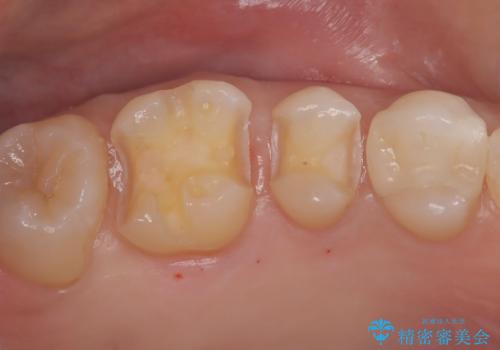

【セラミックインレー】メタルインレーの下が虫歯に

- 定期検診にて虫歯を認め、セラミックインレーにて治療を行いました。

メタルインレーの下には虫歯を認めることが多くありますが、今回のケースでも同じように虫歯を認めました。